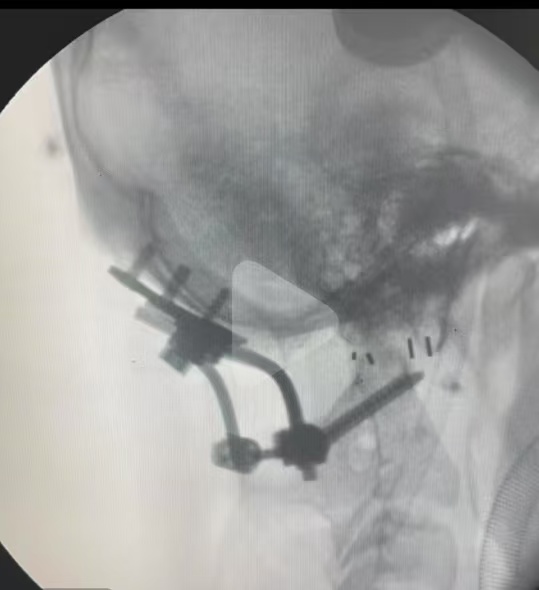

• 日期:2024.11.02

• 术后状况:属于难复位型的,采取后路松解,且用了融合器

• 术后影像: